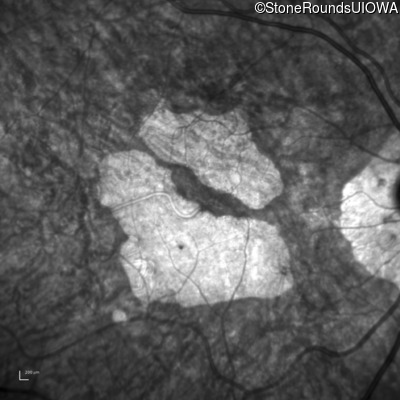

Infrared Fundus Photograph - Left - 20/40 +2

Exemplar